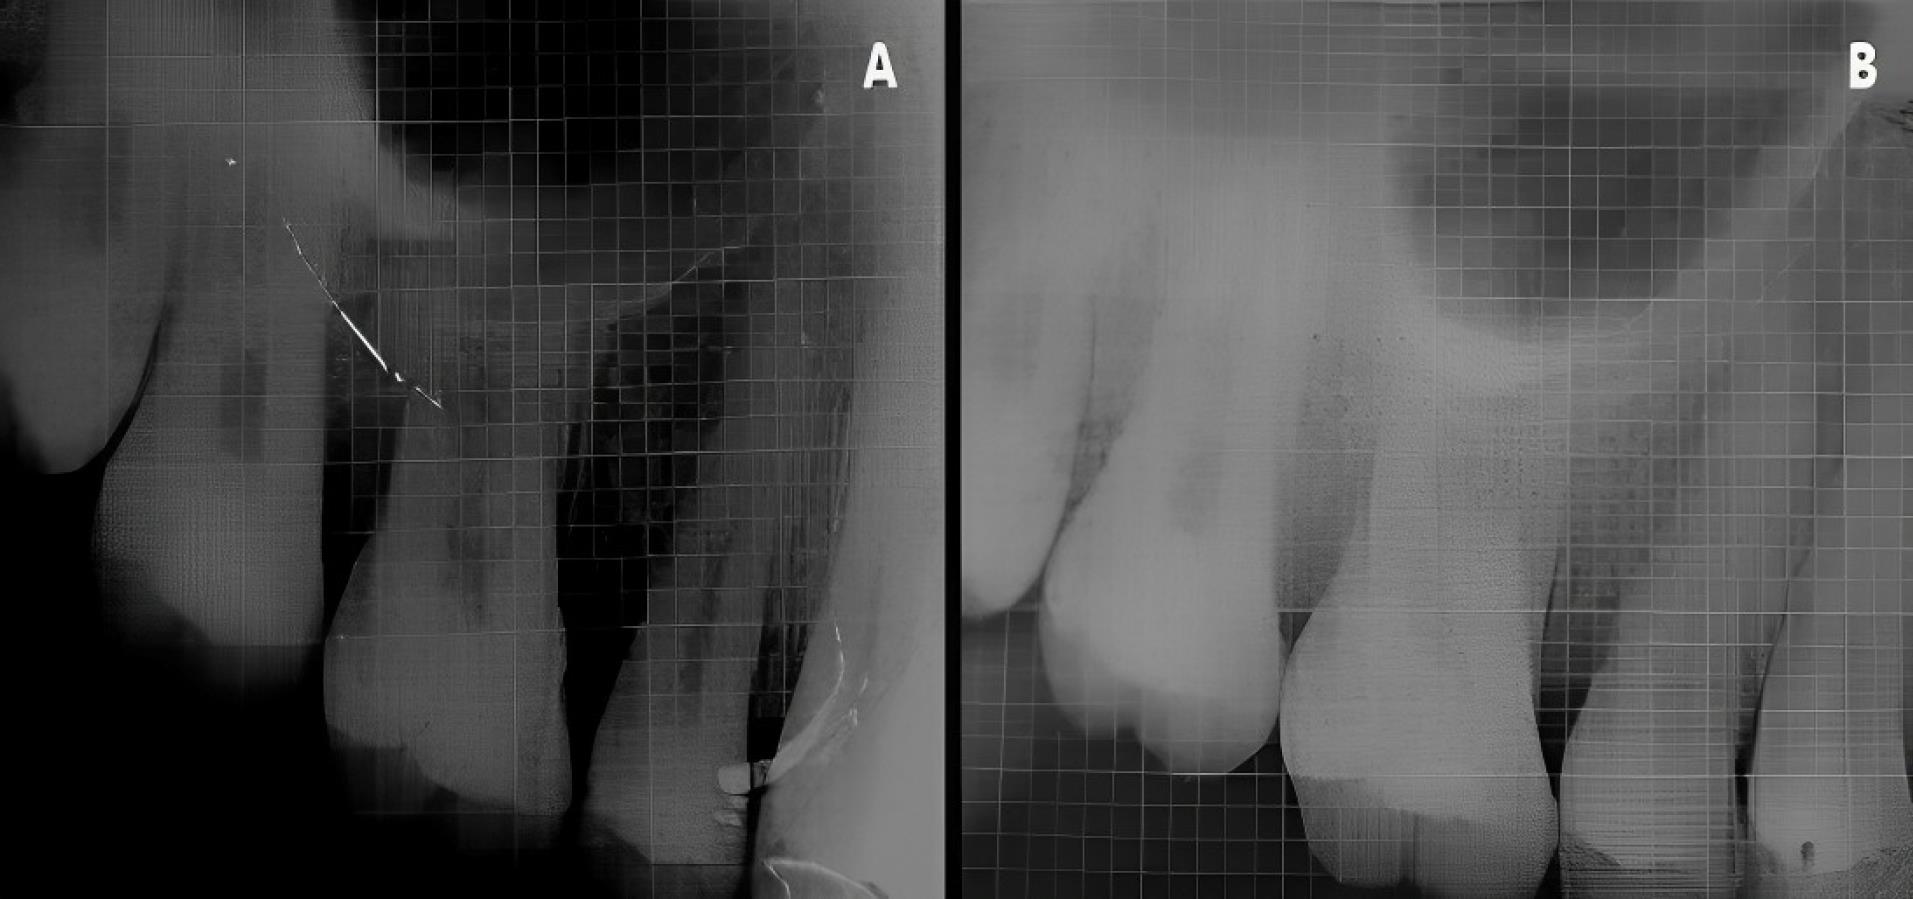

Patients were recalled and reviewed at the first, third, and sixth postoperative months, respectively, and correspondingly. All the clinical measurements were recorded at the third and sixth postoperative months, as shown in Figures 5 and 6, and the postoperative radiographs were taken at the end of six months, as shown in Figures 7 and 8.

Figure 7.

Experimental site A, postoperative-radiographic. A. Baseline. B. 6 months

Figure 8.

Experimental site B, postoperative-radiologic. A. Baseline; B. 6 months